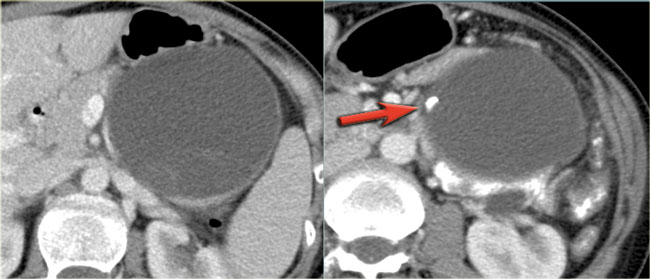

CT-images of a 61 year old woman with weight loss.

There is a large mass in the body of the pancreas that is hypervascular, unlike an adenocarcinoma, with some cystic or necrotic parts.

CT-image of a neuroendocrine tumor with central necrosis.

Sometimes this can simulate a cystic component.

Notice the peripheral enhancement.